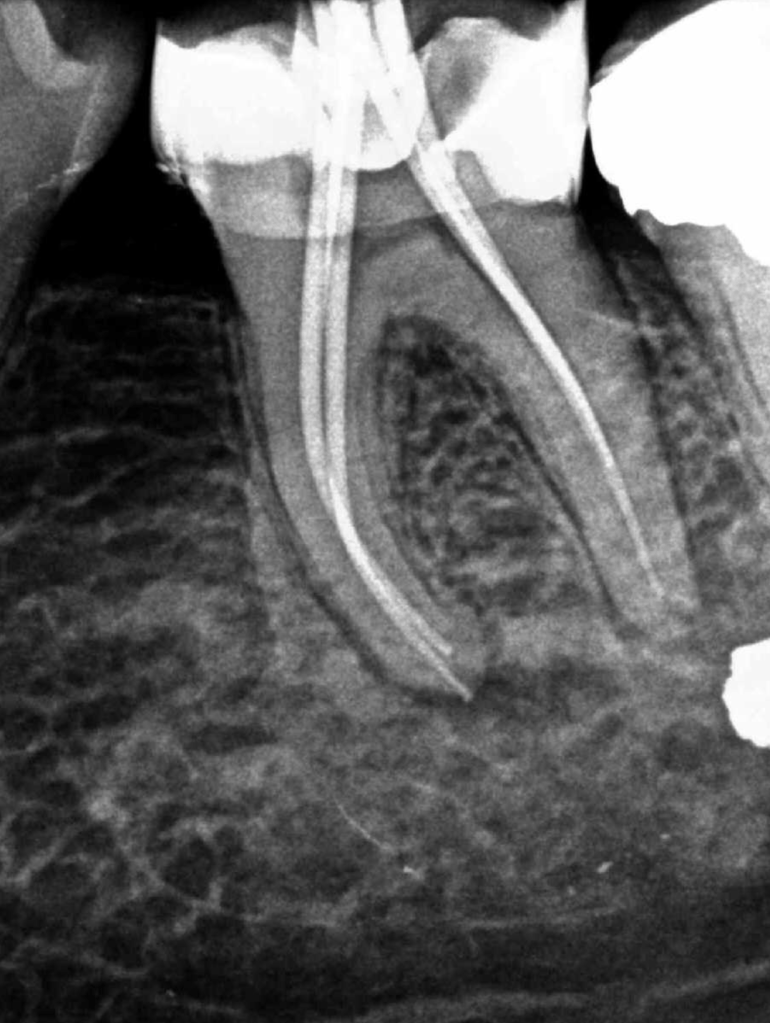

Molar gran curvatura bifurcación palatino